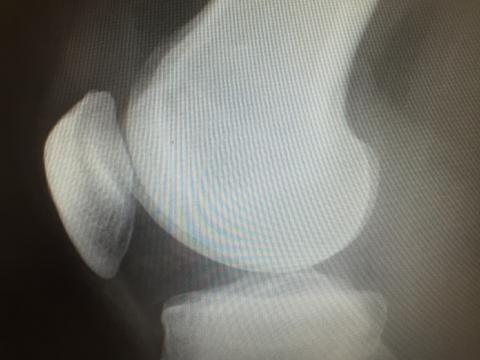

二分膝蓋骨(分裂膝蓋骨)

膝蓋骨(膝のお皿)が、生まれつきで骨が完全にくっつかず、二つ以上のかけらに分かれたまま成長することがあります。

これを二分膝蓋骨または分裂膝蓋骨と呼びます。

意外と日本人でも100人に1〜2人ほどの割合で見られるほど多く、珍しいものではありません。

多くの方は無症状であり、自分の膝が未形成であると一生気づかないこともあります。

しかしスポーツで膝に負担をかけた時や、成長段階で膝に違和感や痛みが生じるようになって気がつく場合があります。

決して深刻にとらえず、このままで改善するのか、リハビリで良くなるのかの見極めが非常に重要です。

膝の専門医なら手術自体も難しくなく、あのドジャース大谷翔平もこの分裂膝蓋骨の手術を受けた後大活躍してます。